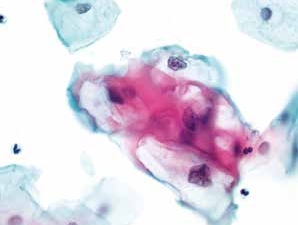

1. 角化型鳞状细胞癌(keratinized squamous cell carcinoma)(图4-50~4-64)

图4-50 角化型鳞癌(高倍、液基、巴氏染色)

肿瘤素质:变性细胞、坏死性碎片及陈旧性出血。此为鳞癌与HSIL的鉴别点之一,浸润性宫颈鳞癌常伴有肿瘤素质。